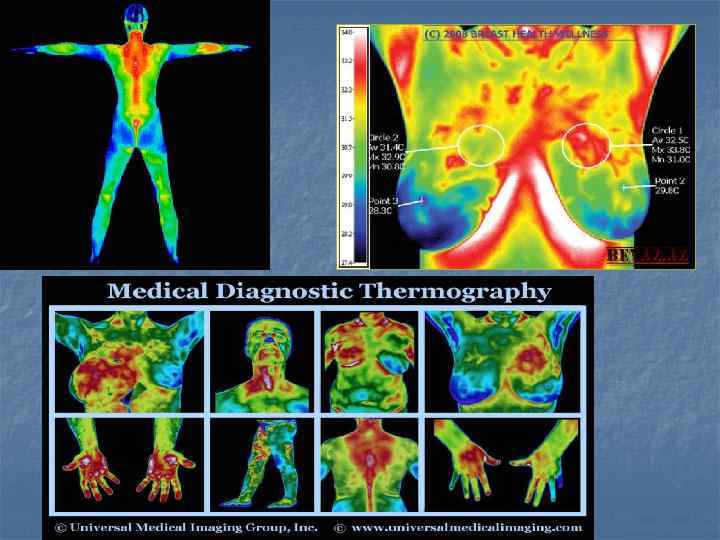

Показания n n n Сосудистая диагностика(тромбоз, диабет) Скрининг опухолевых процессов на ранней стадии(легкие, молочная железа) Определения площади и глубины ожогов Ушибы, артриты, бурситы(активность процесса) Воспалительные заболевания малого таза и брюшной полости